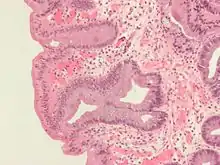

Both macroscopic (from endoscopy) and microscopic positive findings are required to make a diagnosis. Barrett's esophagus is marked by the presence of columnar epithelia in the lower esophagus, replacing the normal squamous cell epithelium—an example of metaplasia. The secretory columnar epithelium may be more able to withstand the erosive action of the gastric secretions; however, this metaplasia confers an increased risk of adenocarcinoma.[15]

Intestinal metaplasia

The presence of goblet cells, called intestinal metaplasia, is necessary to make a diagnosis of Barrett's esophagus. This frequently occurs in the presence of other metaplastic columnar cells, but only the presence of goblet cells is diagnostic. The metaplasia is grossly visible through a gastroscope, but biopsy specimens must be examined under a microscope to determine whether cells are gastric or colonic in nature. Colonic metaplasia is usually identified by finding goblet cells in the epithelium and is necessary for the true diagnosis.

Many histologic mimics of Barrett's esophagus are known (i.e. goblet cells occurring in the transitional epithelium of normal esophageal submucosal gland ducts, "pseudogoblet cells" in which abundant foveolar [gastric] type mucin simulates the acid mucin true goblet cells). Assessment of relationship to submucosal glands and transitional-type epithelium with examination of multiple levels through the tissue may allow the pathologist to reliably distinguish between goblet cells of submucosal gland ducts and true Barrett's esophagus (specialized columnar metaplasia). The histochemical stain Alcian blue pH 2.5 is also frequently used to distinguish true intestinal-type mucins from their histologic mimics. Recently, immunohistochemical analysis with antibodies to CDX-2 (specific for mid and hindgut intestinal derivation) has also been used to identify true intestinal-type metaplastic cells. The protein AGR2 is elevated in Barrett's esophagus[17] and can be used as a biomarker for distinguishing Barrett epithelium from normal esophageal epithelium.[18]